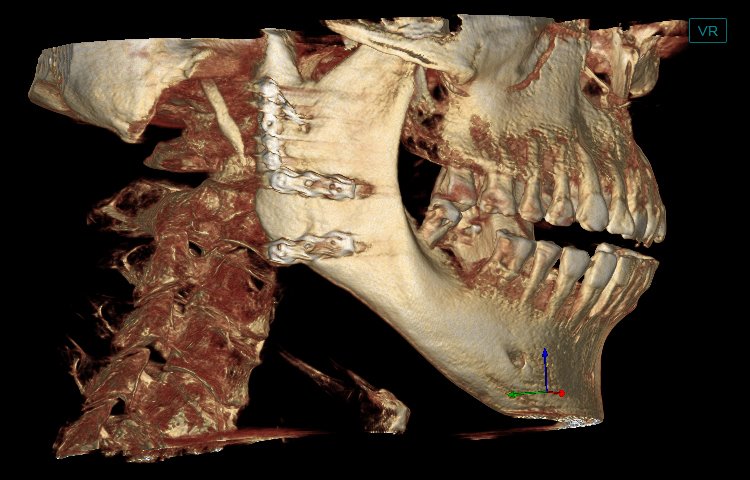

El software de diagnóstico 3D líder de Meyer y el sistema de análisis ortodóntico inteligente adoptan un diseño de UI modular, lo que hace que las funciones del software sean más cercanas a las necesidades clínicas y más fáciles de usar para los médicos, reduciendo significativamente el costo de aprendizaje.

Software de Diagnóstico 3D

MyDentViewer